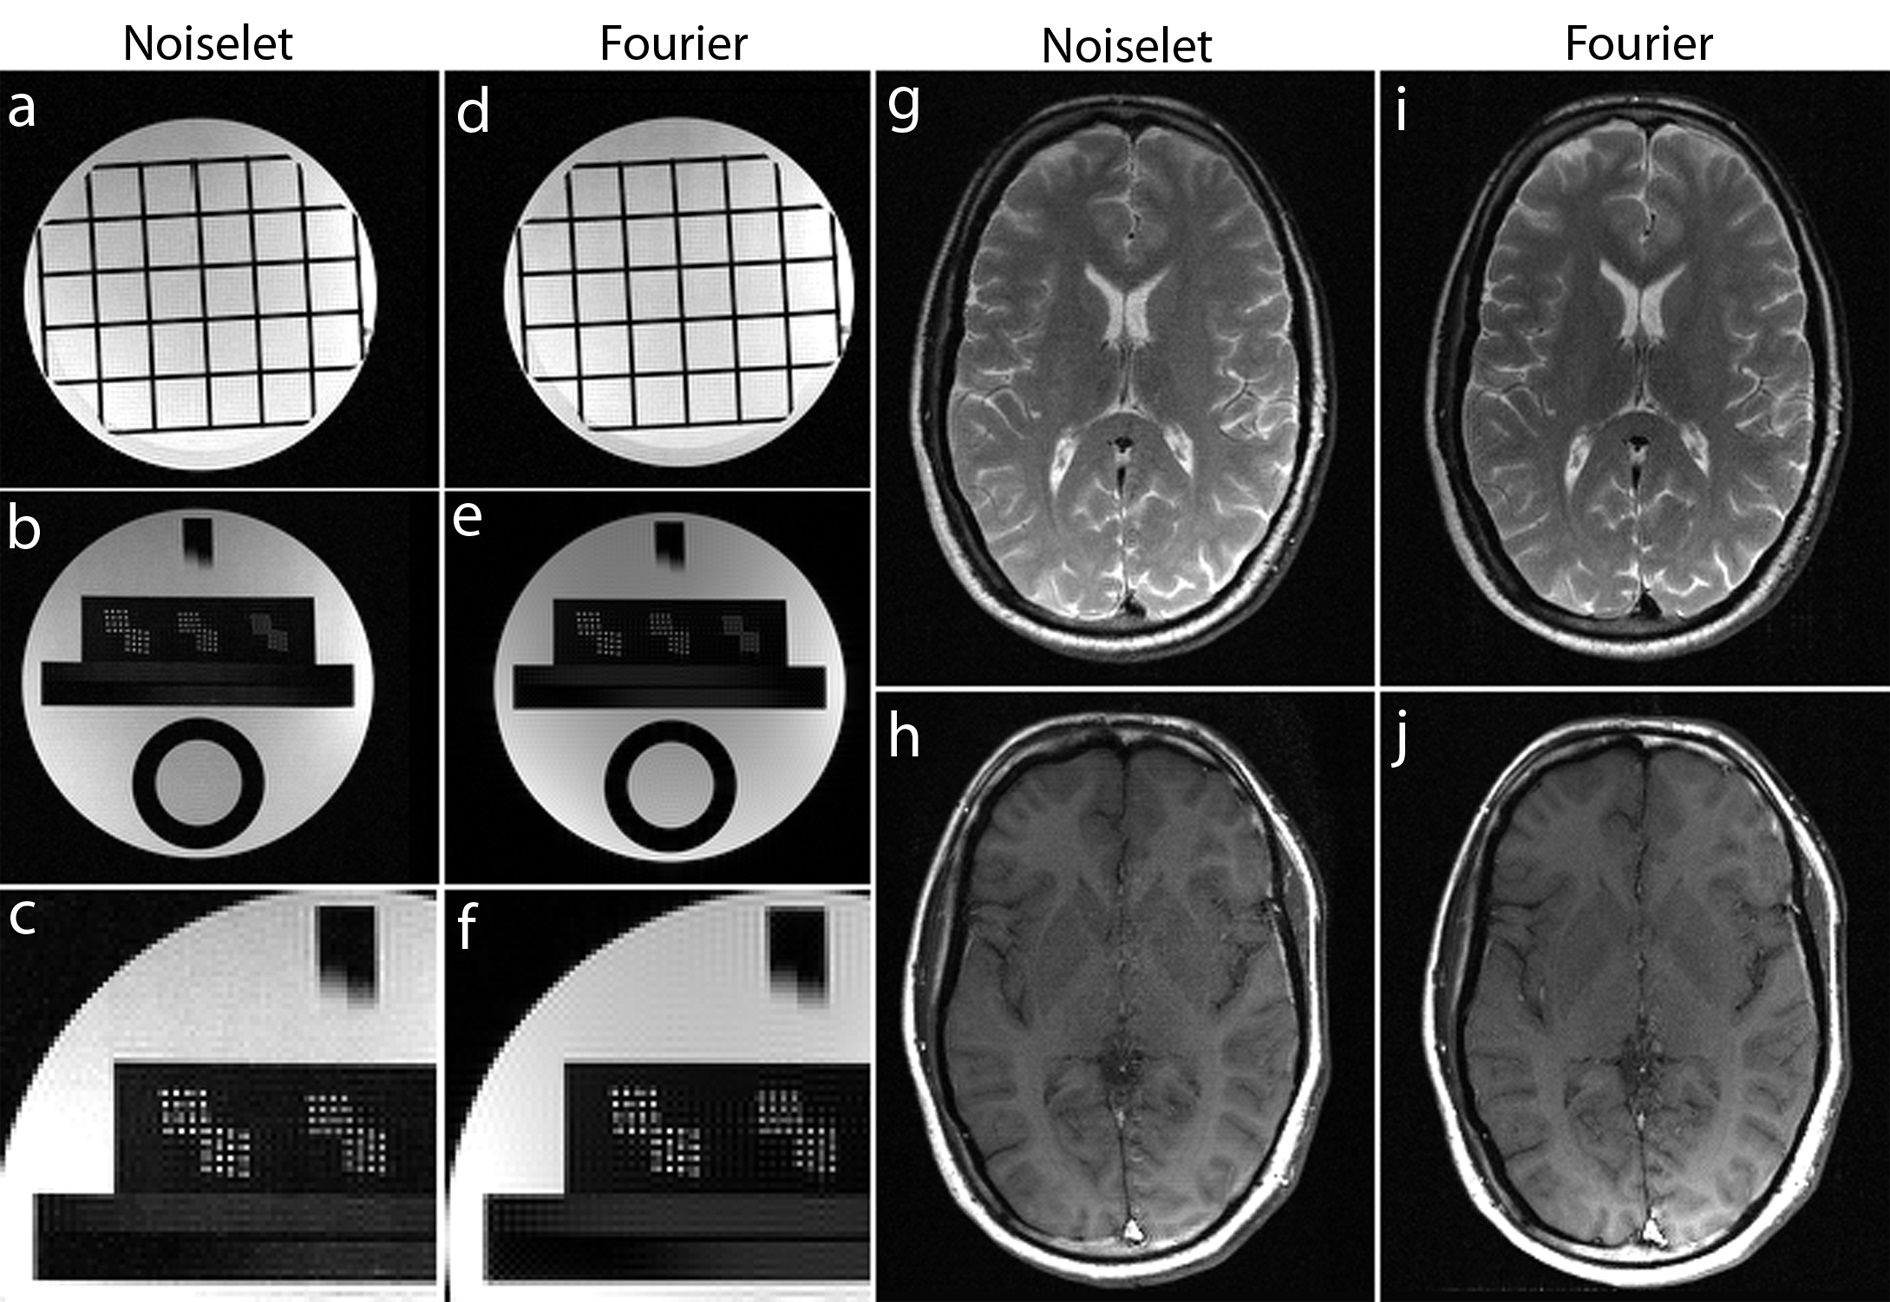

For a noiseless simulation, the reconstructed images for different acceleration factors (4, 8 and 16) are shown in Fig. 8. The difference images in Fig. 8 (d)-(f) and (j)-(l) demonstrate that the error in noiselet encoding is always less than in Fourier encoding, and that the noiselet encoded MCS-MRI reconstruction preserves spatial resolution better than the Fourier encoded MCS-MRI. Fig. 8 (m) and (n) show the zoomed images reconstructed with Fourier encoding for acceleration factors of 8 and 16 respectively, while Fig. 8 (o) and (p) show the zoomed images reconstructed with noiselet encoding for an acceleration factors of 8 and 16 respectively. The zoomed images highlight that the spatial resolution of the noiselet encoded reconstructions outperforms the Fourier encoded reconstructions. Moreover, the spatial resolution provided by the noiselet encoding at an acceleration factor of 16 is comparable to that of the Fourier encoding at an acceleration factor of 8, suggesting that noiselet encoding performs approximately twice as good as Fourier encoding.

Non-Fourier encoding in general is sensitive to field inhomogeneities, but careful design of the sequence and good shimming can result in high quality images. To reconstruct the noiselet encoded data the inverse Fourier transform was taken along the frequency encoding axis and the inverse noiselet transform was taken along the PE axis. To reconstruct the Fourier encoded data, an inverse Fourier transform was taken along both axes. Fig. 11 shows the images reconstructed from the noiselet encoded data and Fourier encoded data sets. These images demonstrate that the noiselet encoding reconstructions are practically feasible and produce artifact free images. Fig. 11(c) shows a zoomed portion of the noiselet encoded image, while Fig. 11(f) shows a zoomed portion of the Fourier encoded image. The zoomed images reveal that the resolution of the image from noiselet encoding with 256 noiselet excitation is the same as that of the image from Fourier encoding with 256 phase encodes. Fig. 11 (g) and (i) show the T2 weighted images for the brain with noiselet encoding and Fourier encoding, respectively. Fig. 11 (h) and (j) show the T1 weighted images for the brain with noiselet encoding and Fourier encoding, respectively. It is evident from the in vivo images that the proposed noiselet encoding is feasible in practice.

To validate the feasibility of the proposed reconstruction method, we performed retrospective under-sampling on the acquired noiselet encoded data and Fourier encoded data to simulate accelerated data acquisition. After retrospective under-sampling, the unconstrained optimization program (10) was solved using the non-linear conjugate gradient method to reconstruct the desired image for different acceleration factors. Fig. 12 (a)-(c) shows the reconstructed images for the acceleration factors of 4, 8 and 16 on the Fourier encoded data while Fig. 12 (d)-(f) shows the corresponding difference images. Similarly, Fig. 12 (g)-(i) shows the reconstructed images for the acceleration factors of 4, 8 and 16 on the noiselet encoded data, and Fig. 12 (j)-(l) shows the corresponding difference images for noiselet encoded MCS-MRI. These results on the acquired data are consistent with the simulation results and indicate that the noiselet encoding is superior to the Fourier encoding in preserving resolution.

Fig. 12 (A-H) shows the zoomed portion of the reconstructed images with Fourier encoding and noiselet encoding. One can distinguish between the small dots in the zoomed images reconstructed with noiselet encoding while it is difficult to distinguish these dots in the images reconstructed with Fourier encoding. This demonstrates that noiselet encoding is able to preserve resolution better than the Fourier encoding. Fig. 13 show the images reconstructed with Fourier encoding and noiselet encoding for various acceleration factors on the data acquired for one axial slice of the brain. Since the SNR of the in vivo images is less than in the phantom images, reconstruction is shown only up to an acceleration factor of 8. The difference images demonstrate that noiselet encoding outperforms Fourier encoding for all acceleration factors. In particular, at the acceleration factor of 8 the image reconstructed with Fourier encoded data has significantly poorer resolution compared to the image reconstructed with noiselet encoded data.